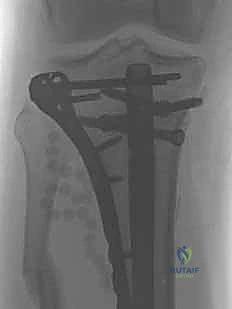

التسمير النخاعي لكسور الساق هو إجراء جراحي رائد لعلاج كسور عظم الساق (الظنبوب) عن طريق إدخال مسمار معدني داخل العظم لتثبيت الكسر. يوفر هذا العلاج استقرارًا قويًا، ويسرع الشفاء، ويقلل من المضاعفات، ويُعد الأستاذ الدكتور محمد هطيف في صنعاء خبيرًا رائدًا فيه.

الخلاصة الطبية السريعة: التسمير النخاعي لكسور الساق (Intramedullary Nailing) هو الإجراء الجراحي الأحدث، والأكثر أماناً، والأعلى فعالية لعلاج كسور عظم الساق (الظنبوب - Tibia). يعتمد هذا التدخل الجراحي الدقيق على إدخال مسمار معدني متطور (مصنوع من التيتانيوم أو الصلب الطبي المقاوم للصدأ) داخل التجويف النخاعي للعظم، مما يعمل كدعامة داخلية لتثبيت الكسر بصلابة فائقة. يوفر هذا العلاج استقرارًا ميكانيكيًا حيويًا ممتازاً، ويسرع من عملية الالتئام العظمي، ويقلل بشكل جذري من المضاعفات مقارنة بالطرق التقليدية القديمة كالجبس أو الشرائح الخارجية. يُعد الأستاذ الدكتور محمد هطيف، أستاذ جراحة العظام والمفاصل بجامعة صنعاء، الخبير الأول والرائد في هذا التخصص الدقيق في اليمن، حيث يجمع بين الخبرة الأكاديمية والسريرية التي تتجاوز 20 عامًا، واستخدام أحدث التقنيات الجراحية (مثل الجراحة الميكروسكوبية ومناظير المفاصل 4K) لضمان عودة المرضى لممارسة حياتهم الطبيعية بأقصى درجات الأمان والمصداقية الطبية.

ولكن مع التطور المذهل في الطب الحديث والهندسة الطبية الحيوية، برز التسمير النخاعي (Intramedullary Nailing) كالمعيار الذهبي (Gold Standard) لعلاج الأغلبية العظمى من كسور الساق. تعتمد هذه التقنية المتقدمة على إدخال مسمار معدني مجوف ومصمم هندسيًا ليتطابق تماماً مع الانحناءات الطبيعية للعظم.

- التثبيت التشابكي (Interlocking): يتم تمرير مسامير صغيرة عرضية عبر العظم والمسمار النخاعي في الطرفين العلوي والسفلي، مما يمنع دوران العظم حول المسمار ويحافظ على طول الساق الطبيعي بدقة متناهية.

4. إدخال المسمار النخاعي والتثبيت النهائي

يتم تمرير مسمار التيتانيوم بدقة داخل العظم. وبمجرد التأكد من موضعه المثالي بالأشعة، يقوم البروفيسور هطيف بإدخال المسامير التشابكية (Locking Screws) العرضية في أعلى وأسفل المسمار لضمان التثبيت المطلق.